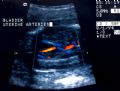

Normal fetal bladder at 18 weeks (left, at arrow). Lovely picture of both uterine arteries around normal bladder (right). This color flow picture documents the presence of the 3 vessel cord with the demonstration of the two uterine arteries coursing around the bladder. - Spine (need two perpendicular views)